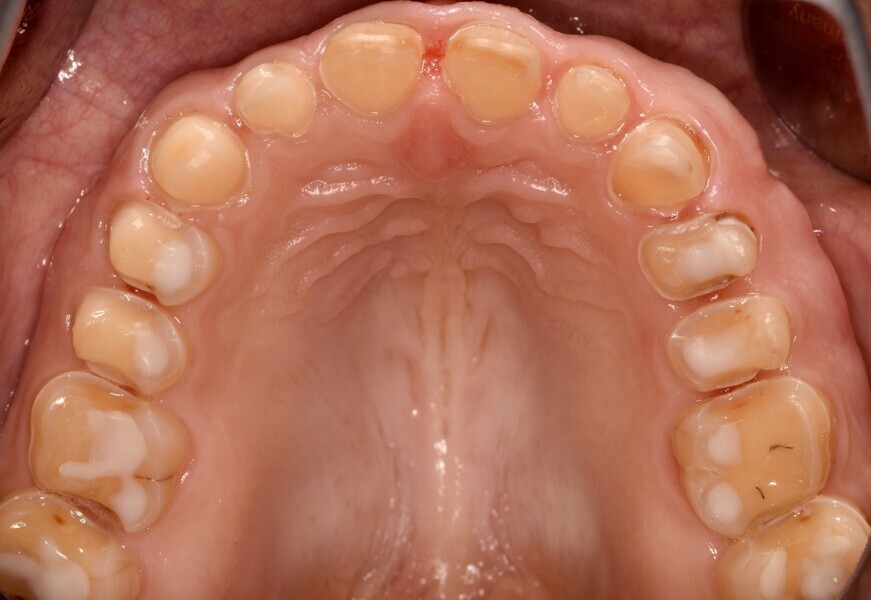

Fig. 1d: Almost complete loss of the occlusal relief in the upper jaw.